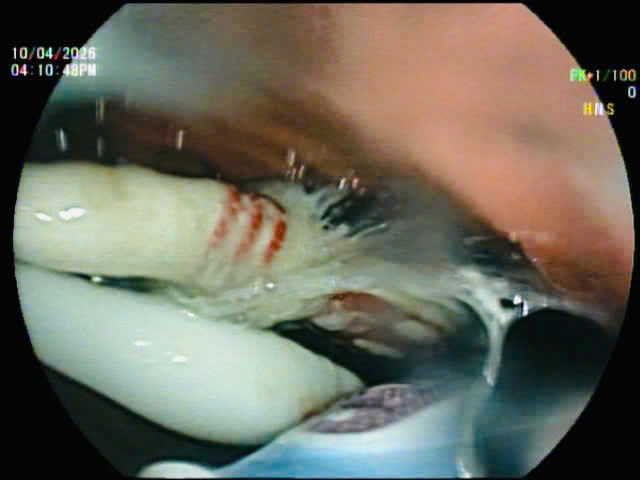

Ngay sau khi tiếp nhận, bệnh nhân được chỉ định nội soi can thiệp. Đội ngũ ê-kíp đã tiến hành gắp thành công toàn bộ 03 dị vật ra khỏi đường tiêu hóa. Việc can thiệp diễn ra thuận lợi, không ghi nhận biến chứng.

ThS.BS. Phạm Như Hiển – Phó Giám đốc Trung tâm Nội soi cho biết, đây là trường hợp hiếm gặp trong thực hành lâm sàng tại Việt Nam khi bệnh nhân nuốt cùng lúc 3 dị vật dài và cứng. Trong đó, dị vật dạng bàn chải đánh răng với chiều dài gần 20cm, có tiềm ẩn nguy cơ cao mắc kẹt trong ống tiêu hóa, gây tổn thương niêm mạc, thủng hoặc tắc nghẽn nếu không được phát hiện và xử trí kịp thời. Dù ca bệnh có tính chất phức tạp, toàn bộ dị vật đã được lấy ra bằng phương pháp nội soi và không cần can thiệp phẫu thuật.